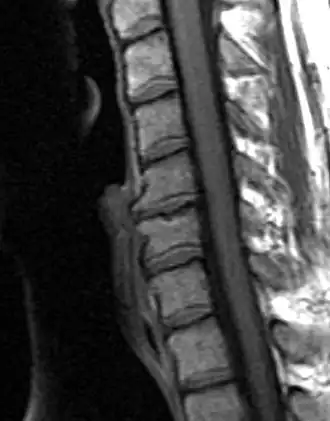

Degenerated disc between C5 and C6 (vertebra at the top of the picture is C2), with osteophytes anteriorly (to the left) on the lower portion of the C5 and upper portion of the C6 vertebral body.